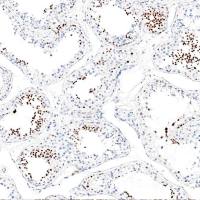

特异性:本试剂可用于体外定性检测冰冻切片肾穿组织中的C3c蛋白。

免疫复合物可通过经典途径和旁路途径激活补体从而引起变态反应造成肾小球组织的损伤。在肾小球疾病中,补体多数通过旁路途径激活,少数经经典途径激活。肾活检中常用的补体抗体为C3、C4、C1q等。C3在人体补体系统是一种中心补体,与肾脏活检中肾小球中的C3反应并沉积,特征地沉积于肾小球外的毛细血管壁。C3表达于肾小球肾炎和耳硬化症中。主要用于肾小球肾炎的免疫复合物种类检测,有助于肾小球肾炎的分类。

在荧光显微镜下对染色后切片进行观察和结果判读。